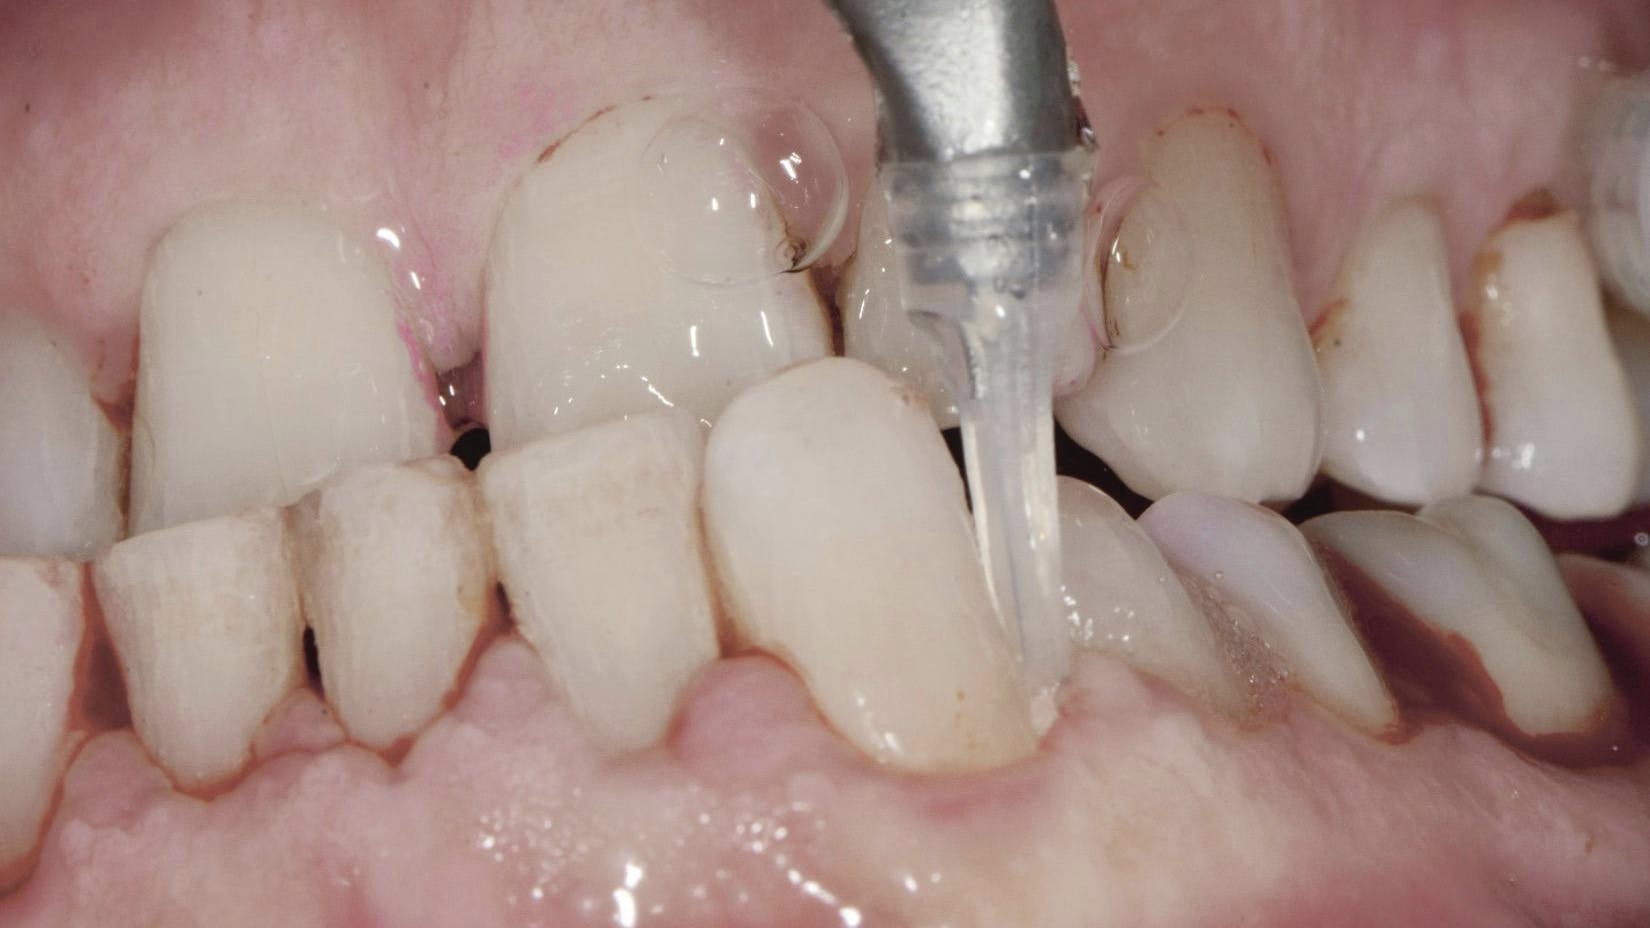

primary

Sponsored

Discover how the HuFriedyGroup PWR Pair is transforming dental hygiene with advanced air polishing and piezo technology—enhancing patient comfort, improving efficiency, and preserving...